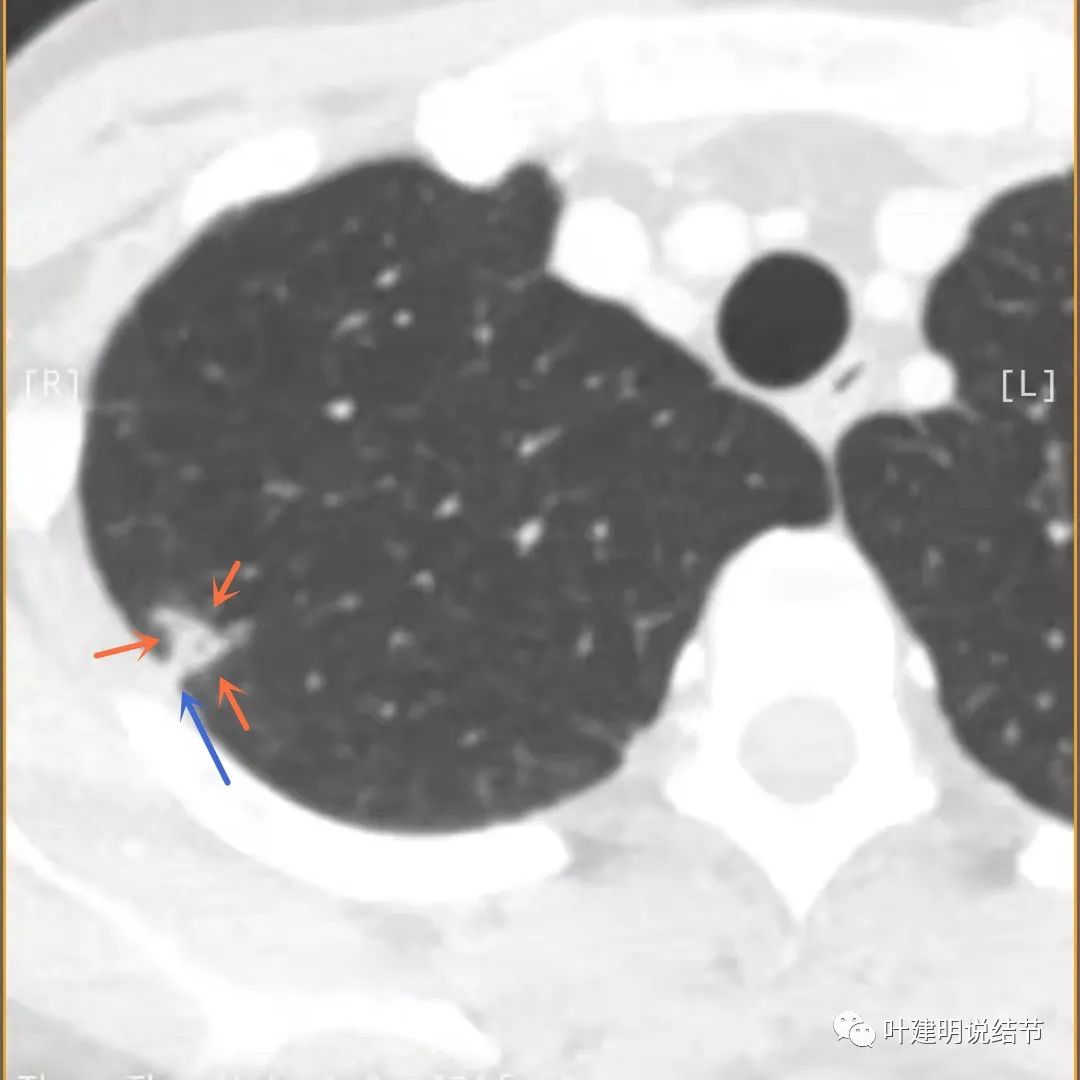

上面是她提供的病史资料,其中最重要的是PPD强阳性!其他主要看影像,我们先来看她2020年7月份的平扫片子(由于片子较多,详细展示是为了同道分析,我在影像特征描述上将只选取部分加以说明):

右肺尖偏实性结节(粉色箭头),邻近胸胸膜明显增厚不平,且广基附在胸壁上(蓝色箭头)

有卫星病灶(绿色箭头)